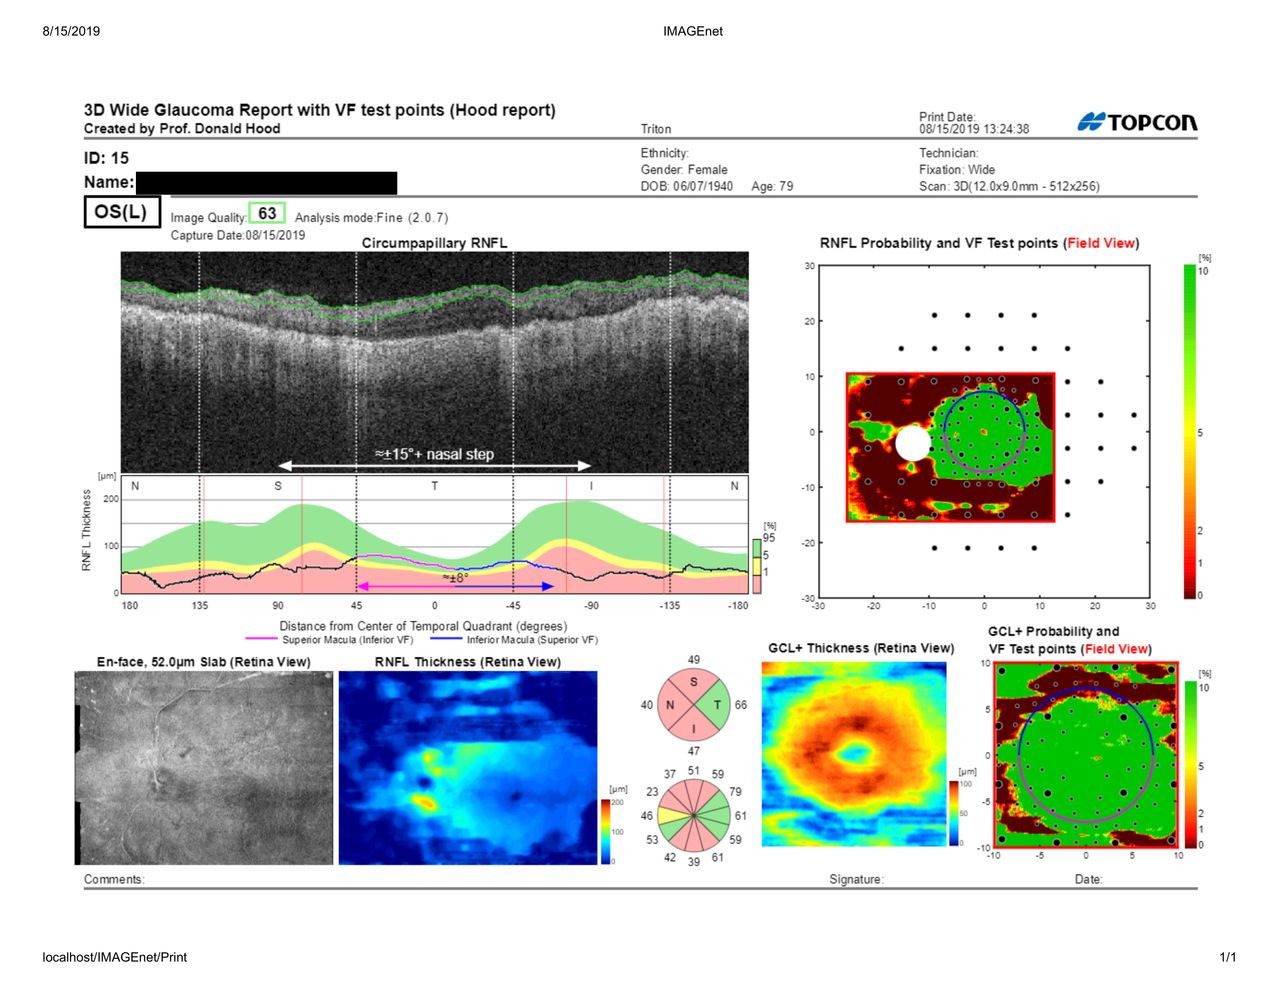

-Tomografía óptica coherente (OCT) Swept Source (Única en Monterrey y su área Metropolitana) de Nervio

Óptico (Glaucoma), Retina, y Segmento Anterior.